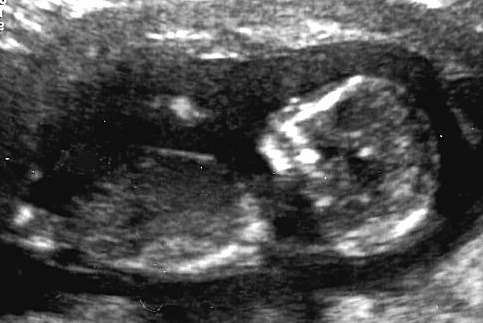

This is for my friend. Is that angled thing a boy nub? Attachment 6562

I can't see a nub sorry

I'm seriously so bad at this. We both thought it was the little angled thing that can be seen above the leg.

It could be, but i am not confident enough to say for sure.

No nub in this image. If I'm looking where I think you are that looks like cord insert.